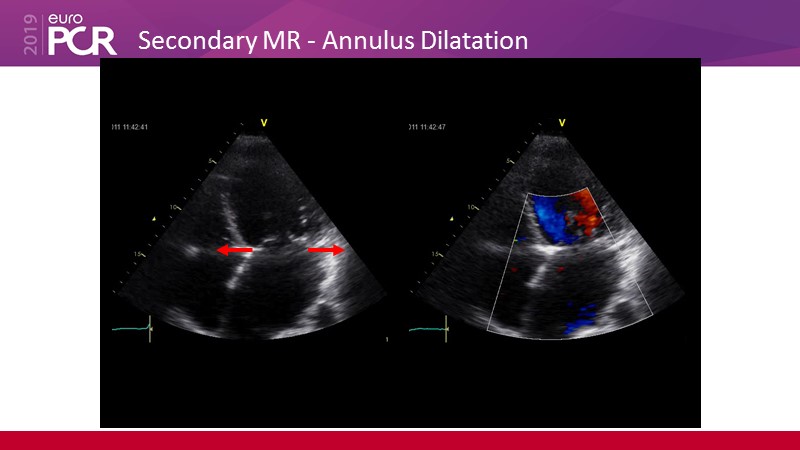

- To learn how will new clinical evidence (MitraFR, COAPT) shape the future of mitral transcatheter interventions

- To learn how will product innovation (Mitraclip NTR / XTR) drive improvement in procedural and clinical outcomes (EXPAND)